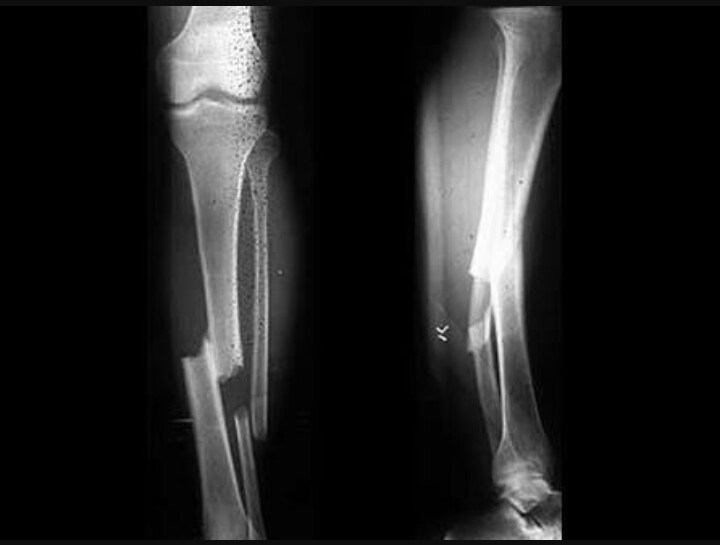

Saat sesi latihan dengan menggunakan motor Trail, Rossi mengalami kecelakaan dan membuat tulang kakinya patah, dan parahnya lagi ini adalah tulang kaki yang pernah patah pada tahun 2010 lalu sehingga pihak dokter tidak bisa memberikan jaminan waktu kapan Rossi bisa kembali mengaspal mengasapi lawan lawannya.